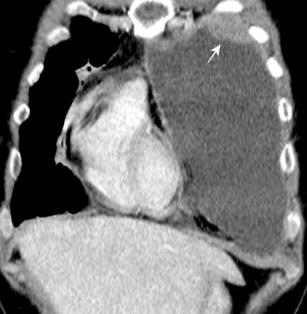

Marzo 2014: Perforación longitudinal distal secundaria a episodio de vómito (síndrome de Boerhaave). Derrame pleural izdo. que evoluciona a empiema.

Wang C-T et al. Tension hydropneumothorax in a Boerhaave syndrome patient: A case report . World J Emerg Med, 2021. Katabathina V et al. Nonvascular, nontraumatic mediastinal emergencies in adults:a comprehensive review of imaging findings. Radiographics. 2011.